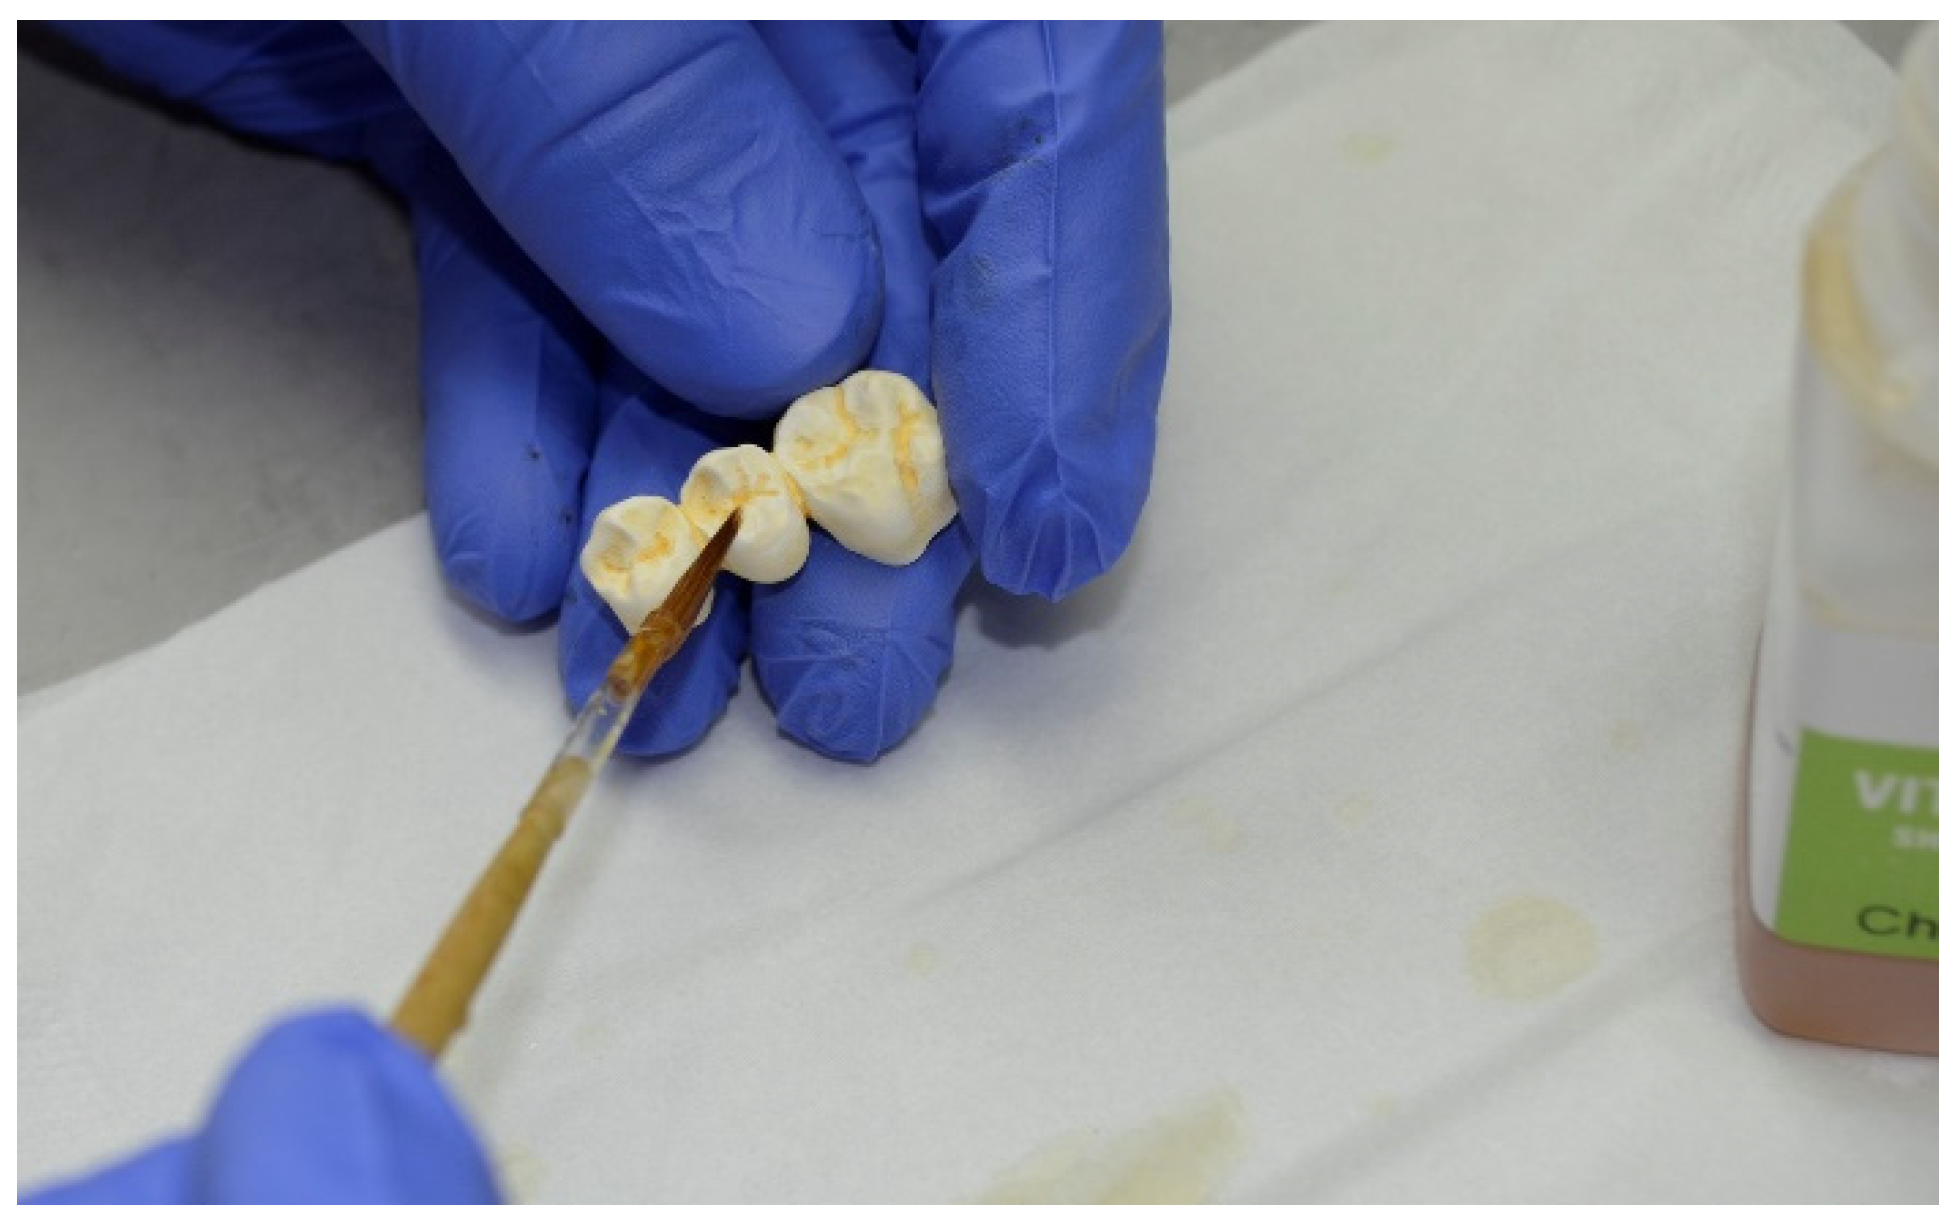

2. Materials and Methods

3. Results

| Surface characterization | VITA akzent plus effect stains, VITA akzent plus glaze LT (both Vita Zahnfabrik) | VITA akzent plus effect stains, VITA akzent plus glaze LT (both Vita Zahnfabrik) | VITA akzent plus effect stains, VITA akzent plus glaze LT (both Vita Zahnfabrik) | VITA akzent plus effect stains, VITA akzent plus glaze LT (both Vita Zahnfabrik) | Signum Composite (Kulzer), Optiglaze Color (GC) | Signum Composite (Kulzer), Optiglaze Color (GC) | Signum Composite (Kulzer), Optiglaze Color (GC) |

| Others | - | - | - | - | D2 individualized with Optiglaze Color (GC) to better fit D3 | - | opaquer needed to cover the framework before veneering |